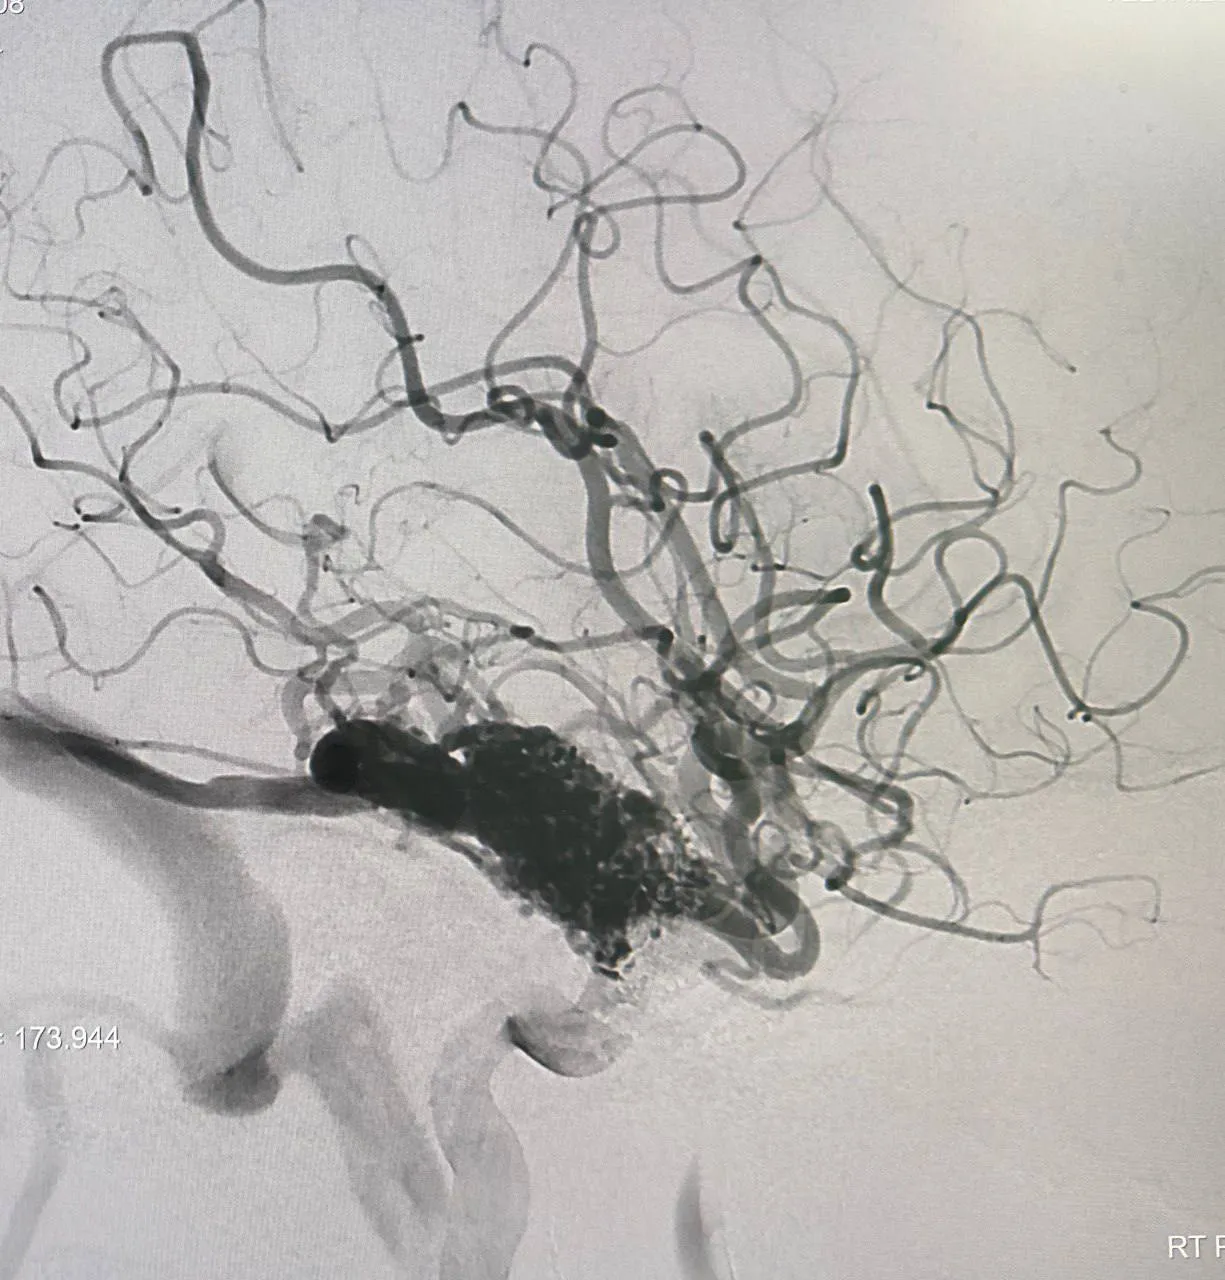

Во время операции врачам удалось пройти «клубок сосудов» тонким катетером и залить специальной клеевой композицией кровоточащий сосуд. Такие действия позволят снизить риск кровотечений в дальнейшем.